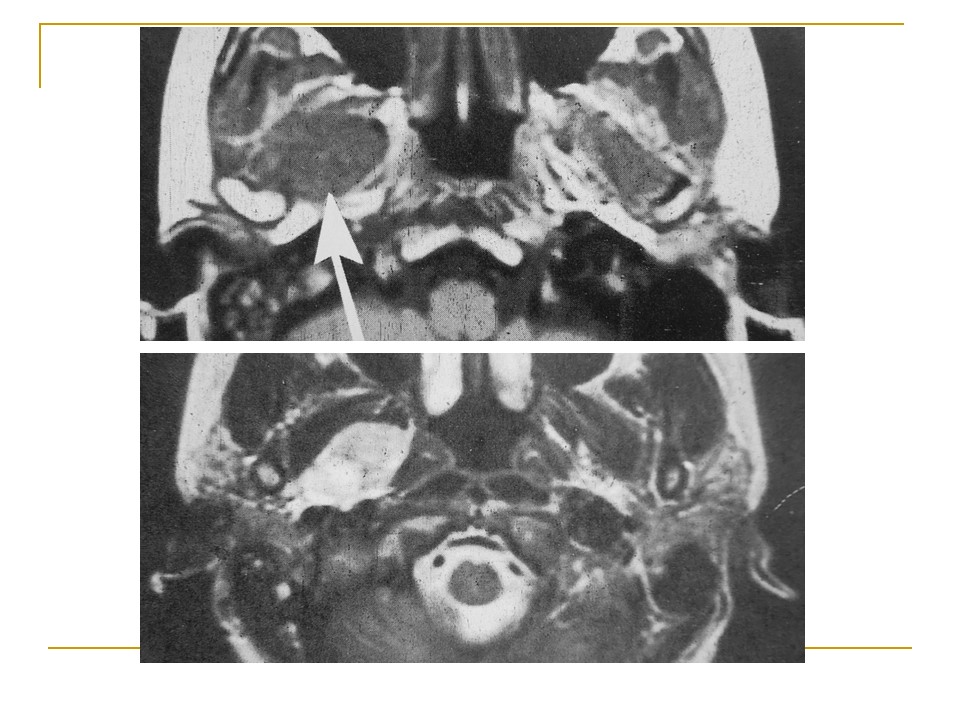

腮腺混合瘤MRI表现